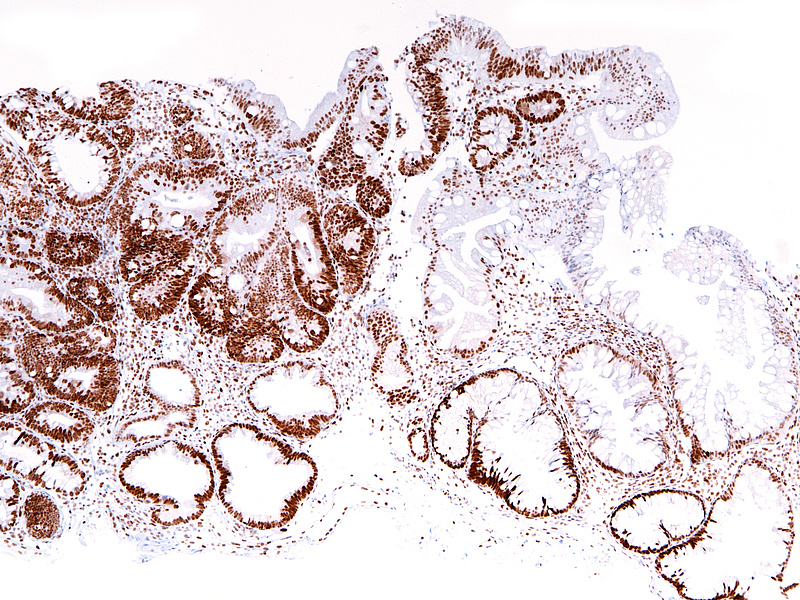

Ascending colon polyp in a 79-year-old male.

Unclassified serrated adenoma.

The ascending colon polyp is a serrated polyp characterized by a combination of two morphological patterns which are sessile serrated lesion (SSL) and traditional serrated adenoma (TSA). The former is formed by architecturally distorted serrated crypts with deep serrations, basal crypt dilatation and lateral growth along the muscularis mucosae (Panels A-B). Some foci of stromal proliferation resembling perineural cells are also seen within this component (Panel C). The TSA component has typical slit-like serrations, lined by tall columnar cells with intensely eosinophilic cytoplasm and pencillate nuclei (Panels D-E). Abrupt transition to dysplastic mucosa and glands are present, where the glands display more complex and crowded architecture with little intervening lamina propria (Panel F). The dysplastic cells show features of adenomatous dysplasia characterized by columnar cells with enlarged hyperchromatic nuclei, pseudostratification and reduced goblet cells (Panel G). In some areas, the cells display high grade cytology with more rounded nuclei and loss of polarity. MLH1 immunostaining was preserved in both the non-dysplastic and dysplastic glands with higher intense staining seen in the latter (Panel H).

The variable morphological features that is present in this polyp makes it difficult to delineate whether this polyp represents a SSL with dysplasia (SSLD) or TSA with overt (adenomatous) dysplasia. Retained MLH1 staining pattern was also not helpful in this case as it is known that both adenomatous and serrated- type dysplasia in SSL will show preserved MLH1 staining. Therefore, when dealing with such complexity in a polyp, it is best to classify such polyp as unclassified serrated adenoma (USA).